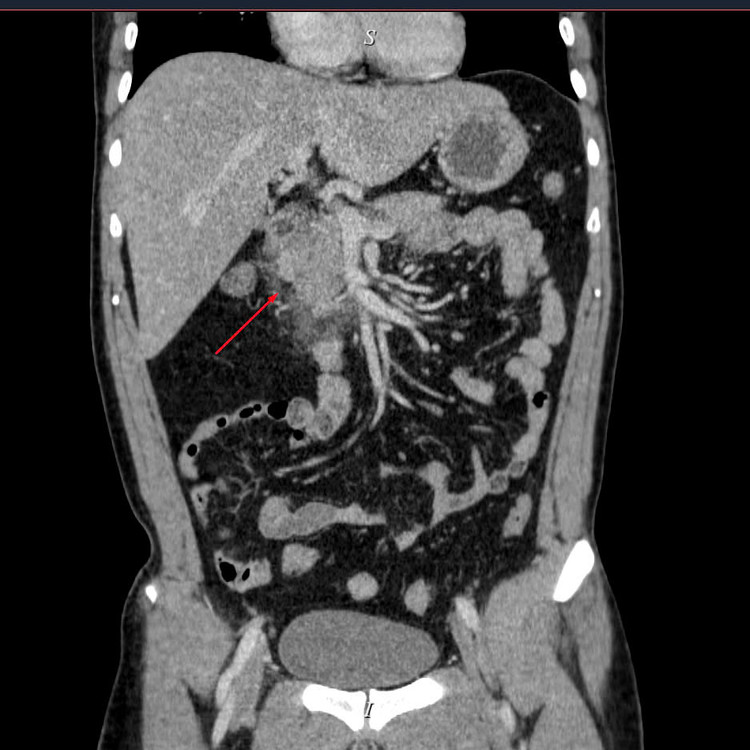

| Viêm tụy cấp trên phim chụp - Ảnh BVCC |

Kết quả chụp CT Scanner đa dãy ổ bụng có thuốc cho thấy: Hình ảnh viêm tụy cấp Balthazar D, mCTSI 4 điểm, xét nghiệm máu triglycerid >73 mmol/ l, khí máu có tình trạng toan Lactat>2. Nhận thấy đây là tình trạng viêm tụy cấp nặng do tăng triglyceride, các bác sĩ khoa Hồi sức cấp cứu Bệnh viện Đa khoa Hùng Vương đã tiến hành lọc máu hấp phụ cho bệnh nhân với mục tiêu là giảm triglycerid, và giảm phản ứng viêm.